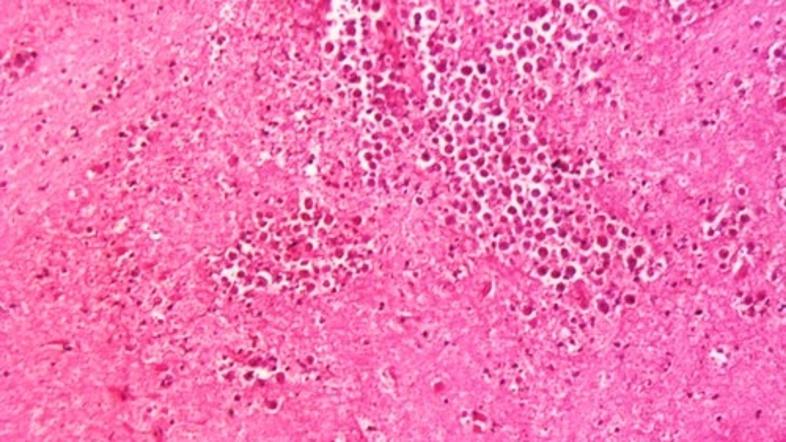

Iz tega vodovodnega sistema se oskrbujejo mesta Reserve, Garyville in Mt. Airy. Naegleria fowleri  pri človeku povzroča primarni amebni meningoencefalitis. Ameba povzroči hudo vnetje možganov, razžiranje živčnega tkiva, kar pripelje do smrti v enem do dvanajstih dni po izpostavljenosti amebi. Bakterija najbolje uspeva v topli sladki vodi, najdemo jo lahko v rekah in jezerih. Do možganov potuje preko nosnih membran, s človeka na človeka se ne prenaša.